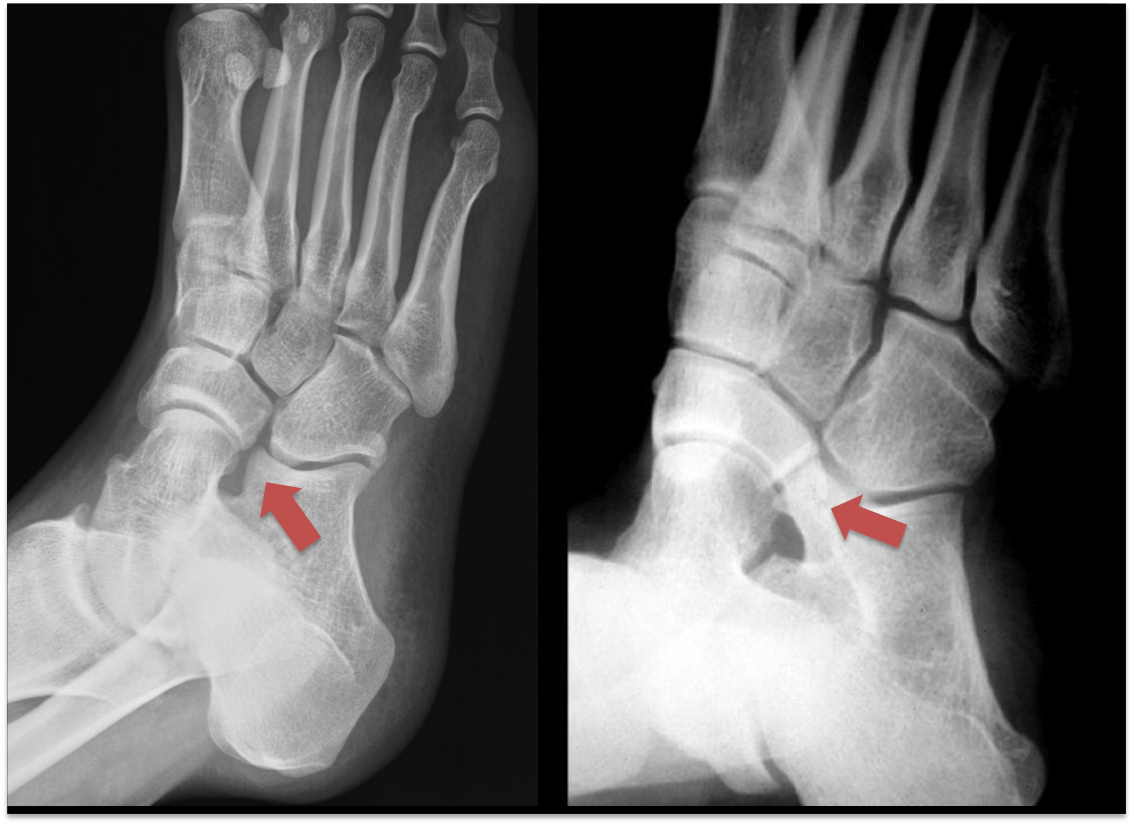

The calcaneo-navicular coalition is best seen on xray, look below on the left is a normal foot xray the arrow points to a normal disconnect between two bones, on the right please compare and see a bone connection.